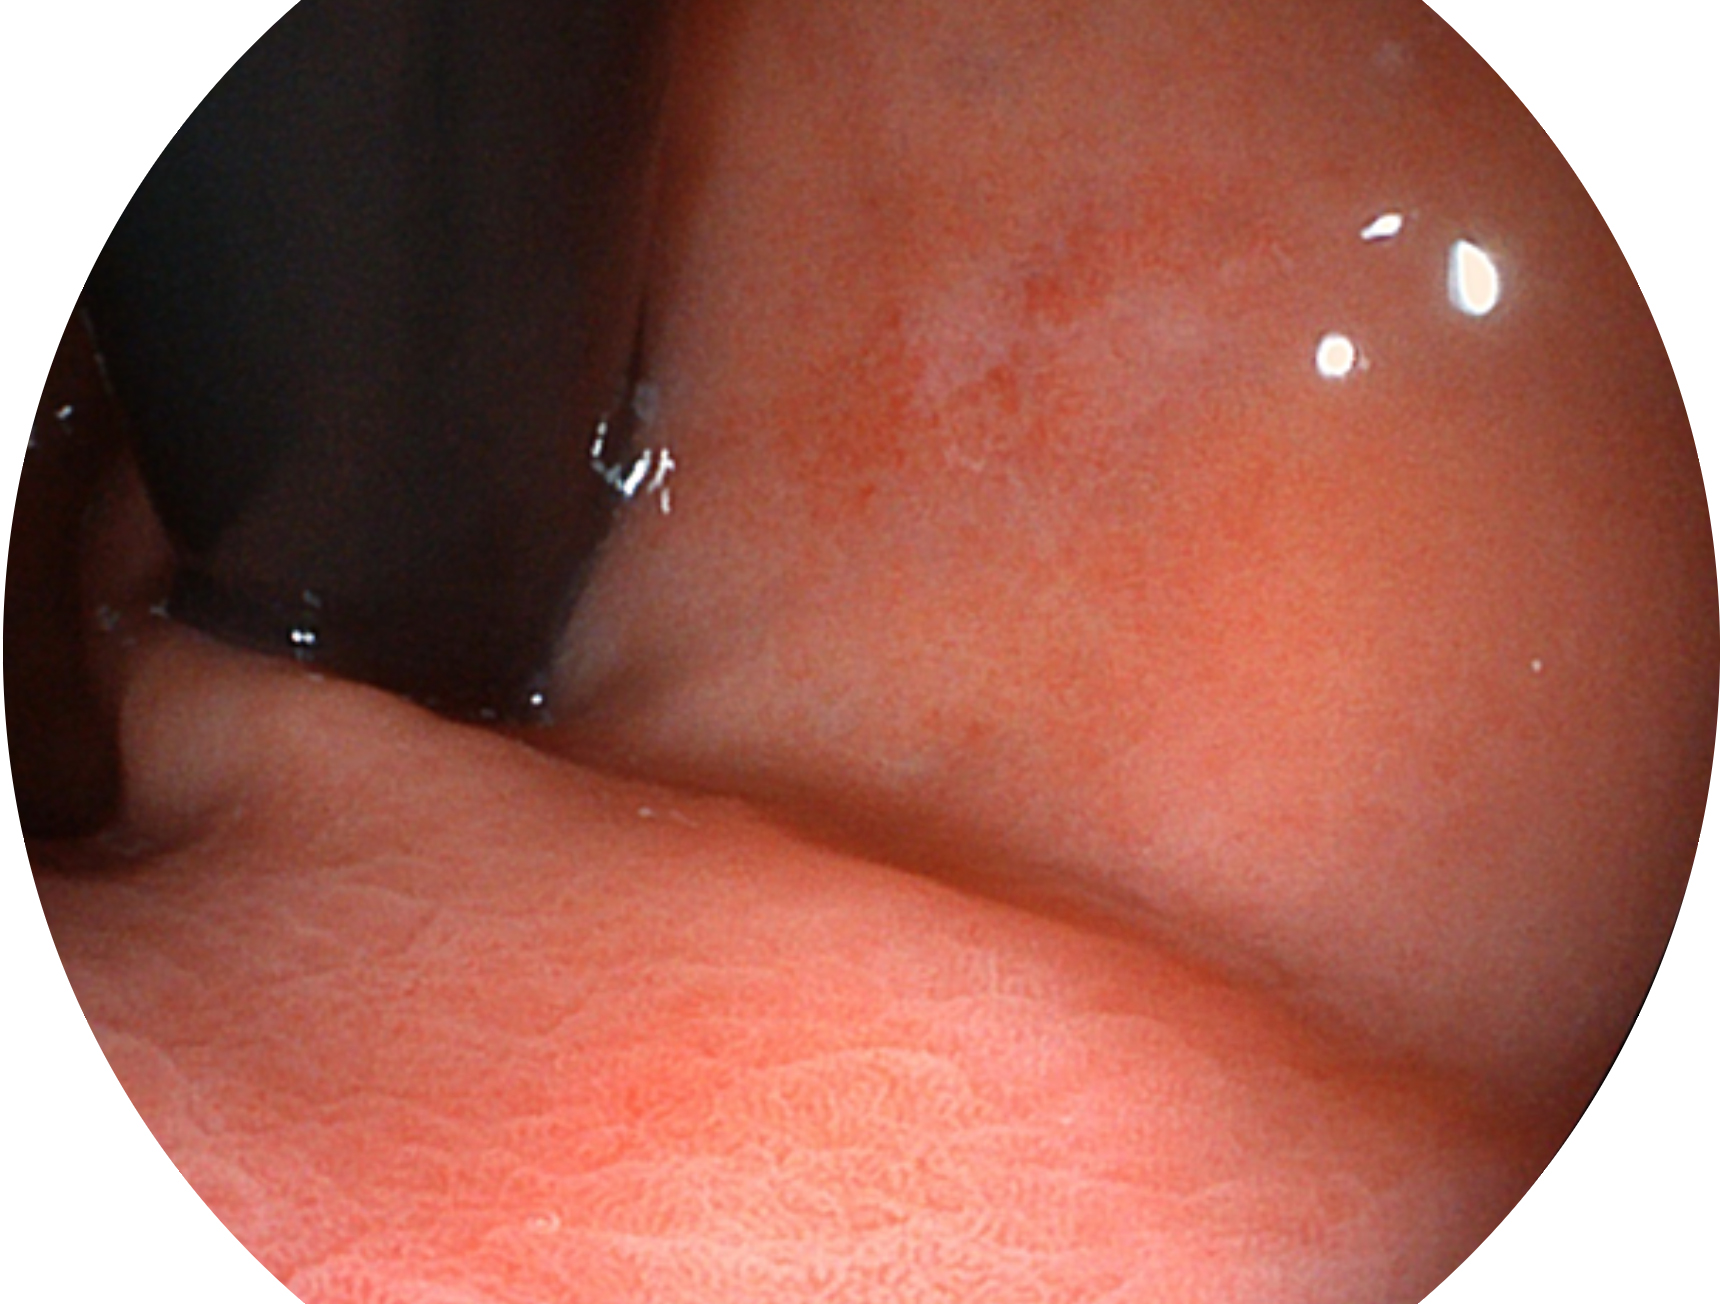

MILE米乐集团官网新开发的内镜染色技术,主要是基于多波长LED 光源的开发,VLS-55Q 四波长LED 光源是由四个不同颜色的LED光按照相应照明模式所规定的特定发光比例进行合束后形成,合束后形成的照明光的光谱由红光、绿光、蓝光及蓝紫光这四个不同的波段范围构成。具有更高光谱自由度,通过光谱比例的控制,实现了聚谱成像技术,英文全称为“Spectral Focused Imaging, SFI”,缩写为“SFI”和光电复合染色成像技术,英文全称为“Versatile Intelligent Staining Technology, VIST”,缩写为“VIST”。